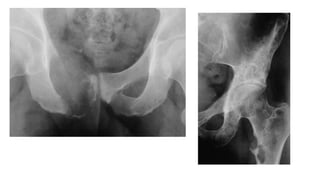

Osteomalacia

🠶Loss of bone density

🠶Thinning of trabeculae and cortex

🠶Looser`s zones (pseudofractures): commonest in the

scapulae, medial aspects of the femoral necks and

in the pubic rami.

🠶Bone deformity: biconcave vertbebra. Bowing of

long bones. T

riradiate pelvis

Hyperparathyroidism:

🠶Brown tumours: seen more in primary type. Lytic lesions,

single or multiple, of varying size and may be expensile.

They occur most commonly in the mandible and pelvis.

Osteomalacia 🠶Loss of bonedensity 🠶Thinning of trabeculae and cortex 🠶Looser`s zones (pseudofractures): commonest in the scapulae, medial aspects of the femoral necks and in the pubic rami. 🠶Bone deformity: biconcave vertbebra. Bowing of long bones. T riradiate pelvis

Hyperparathyroidism: 🠶The hallmark ofhyperparathyroidism issubperiosteal bone resorption, particularly at the radial side of the middle phalanges and at the tips of the terminal phalanges. 🠶There may also be resorption of the outer ends of the clavicles. 🠶Soft tissue calcification, vascular calcification and chondrocalcinosis:more in the secondary type 🠶Brown tumours: seen more in primary type. Lytic lesions, single or multiple, of varying size and may be expensile. They occur most commonly in the mandible and pelvis.